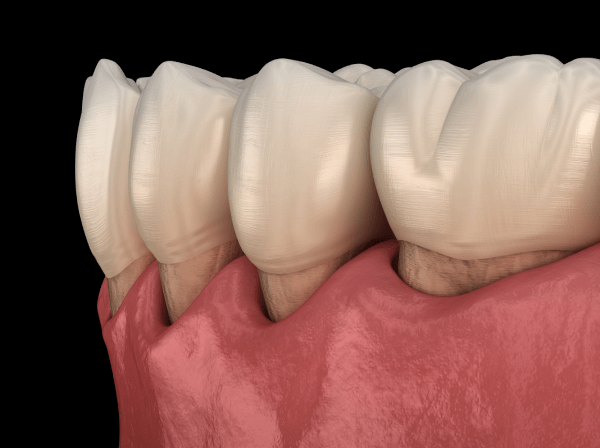

Gum disease is an infection in the gums, and therefore also in the bones once it gets to be rather severe. This causes bone loss down into and around each of the teeth. When that happens, bacteria gets into your bone and blood stream and can become a system problem, not just an oral problem. Gingivitis is especially common during the second to eight months of pregnancy.

How To Tell If Your Gums Are Unhealthy

A simple test is to vigorously floss between all of you teeth. Is there any blood on the floss? If so, you have gingivitis at least, and possibly more progressive gum disease. Healthy gums do not bleed when you clean your teeth with brushing or flossing. If your teeth and gums bleed when you brush and floss, you are at risk for serious illness.